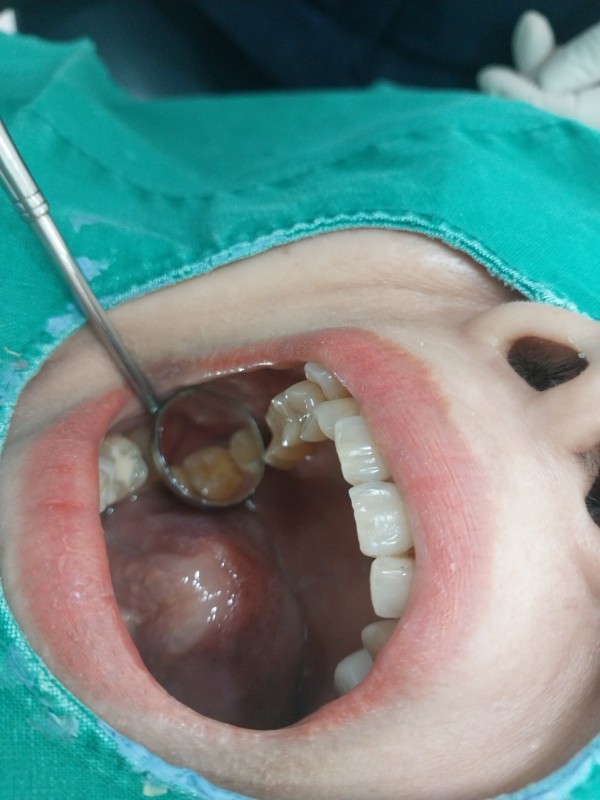

임플란트는 자연치아를 대체하는 훌륭한 치료 옵션이지만, 오랜 기간 기능을 유지하려면 적절한 관리가 필수입니다. 본 칼럼에서는 임플란트 주위 조직 보호와 보철물 수명을 연장하는 실천법을 단계별로 정리했습니다.

정기적 자가 관리와 전문 스케일링으로 임플란트 주변 염증을 예방하고, 과도한 교합력을 분산하여 보철물 파절 및 나사 풀림을 방지할 수 있습니다. 구강 위생 유지로 임플란트 수명을 획기적으로 연장합니다.